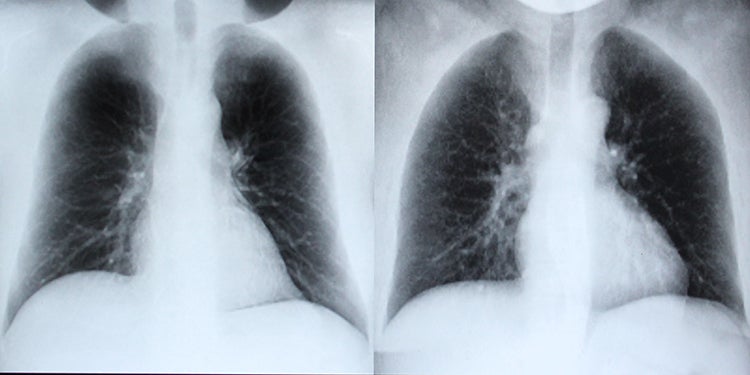

Fourth-year students Alex Chang and Abhishek Moturu looked at training an AI neural network to detect lung cancer using X-ray images. Their project was driven by a lack of training data from which the neural networks could learn.

Under the supervision of Ken Jackson, a professor of computer science, and Dr. Joseph Barfett, a project investigator with the Li Ka Shing Knowledge Institute at St. Michael’s Hospital, Moturu and Chang developed a system that could build a repository of computer-generated X-rays for the neural network to use to detect nodules, a classification of tumours that are less than three centimetres in diameter.

“There simply aren’t enough X-rays, or they’re sometimes in inconsistent formats, so the idea is to create an automatic way of producing a large number of diverse X-rays in order to train this network,” says Moturu.

Using CT scans as a 3D model, simulated nodules of different shapes and sizes can be placed into these scans, creating a dataset of synthetic frontal chest X-rays. The neural network learns from these simulated scans in order to recognize lung cancer at early stages.

“You can think of the CT scan as a 3D array of voxels, which is the 3D equivalent of a pixel. Each voxel has its own attenuation or radiodensity, and we can trace rays going through voxels by calculating distances,” says Chang. “Using formulas, we can compute the intensity lost along each ray. We end up with an X-ray that is unique and we can keep placing different nodules to create more simulated X-rays.”

A real X-ray (shown left) and a computer-generated X-ray simulated by Abhishek Moturu and Alex Chang (image courtesy of the researchers)